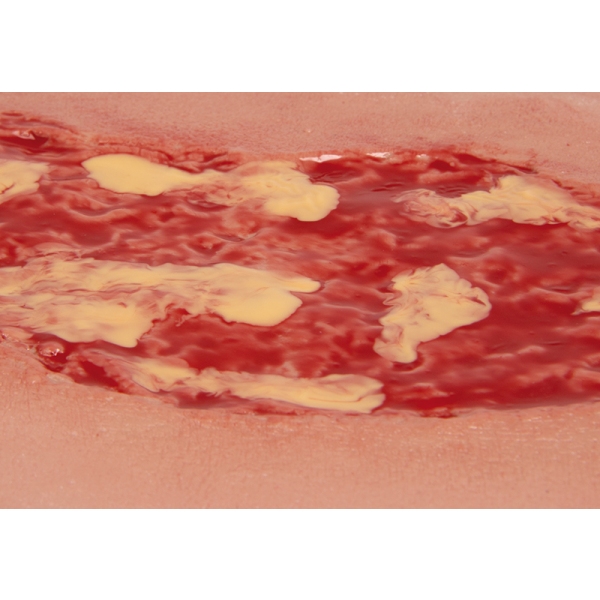

Mulaža rane venska razjeda na nogi, velika, faza eksudacije

Ta samolepilna rana predstavlja vensko razjedo na nogi, defekt snovi v tkivu spodnjega dela noge, ki je posledica kroničnega venskega popuščanja. Prikazana faza eksudacije predstavlja najpogostejšo ulkusno bolezen (60 % do 80 % vseh ulkusnih bolezni) v nezdravljenem stanju. Med čiščenjem je treba odstraniti fibrin in prekomerni ekssudat iz rane. Ta velika rana je kot nalašč za lepljenje na spodnjem delu noge in se sama prilepi. Za daljšo uporabo jo je mogoče pritrditi s posebnim kožnim lepilom. Vsi materiali, uporabljeni v tem izdelku, so dermatološko neškodljivi.